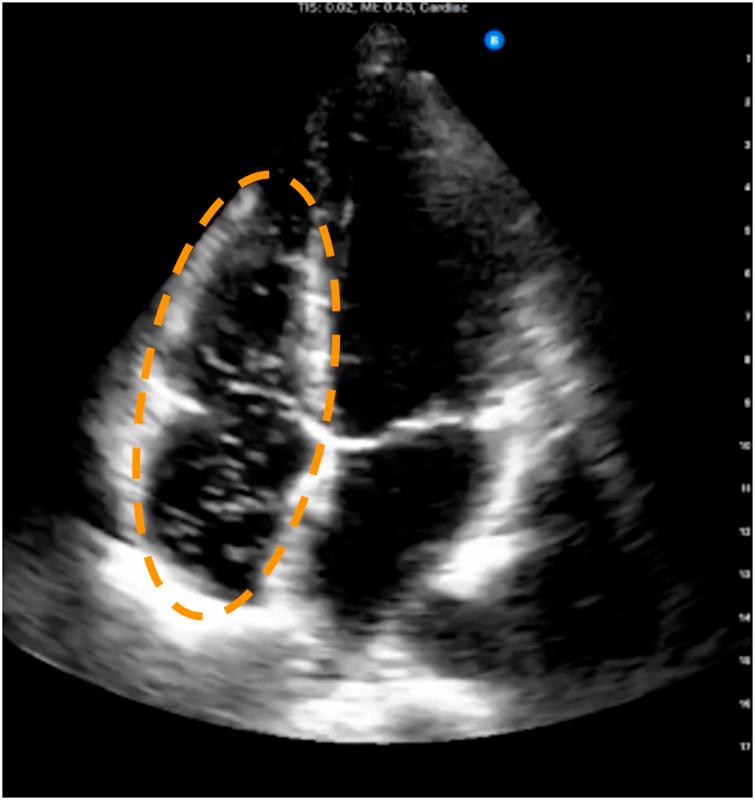

Decompression sickness (DCS) can result from the growth of bubbles in tissues and blood during or after a reduction in ambient pressure, for example in scuba divers, compressed air workers or astronauts. In scuba diving research, post-dive bubbles are detectable in the venous circulation using ultrasound. These venous gas emboli (VGE) are a marker of decompression stress, and larger amounts of VGE are associated with an increased probability of DCS. VGE are often observed for hours post-dive and differences in their evolution over time have been reported between individuals, but also for the same individual, undergoing a same controlled exposure. Thus, there is a need for small, portable devices with long battery lives to obtain more ultrasonic data in the field to better assess this inter- and intra-subject variability. We compared two new handheld ultrasound devices against a standard device that is currently used to monitor post-dive VGE in the field. We conclude that neither device is currently an adequate replacement for research studies where precise VGE grading is necessary.

减压病(DCS)可能源于环境压力降低期间或之后组织和血液中气泡的形成,比如在水肺潜水员、压缩空气作业人员或宇航员身上。在水肺潜水研究中,潜水后通过超声检查可在静脉循环中检测到气泡。这些静脉气体栓子(VGE)是减压应激的一个指标,大量的VGE与减压病发生概率增加相关。VGE在潜水后数小时内常可观察到,并且据报道,个体之间以及同一个体在经历相同的受控暴露时,其随时间的演变情况存在差异。因此,需要小型、便携且电池续航时间长的设备,以便在现场获取更多超声数据,从而更好地评估这种个体间和个体内的变异性。我们将两款新型手持式超声设备与目前在现场用于监测潜水后VGE的标准设备进行了比较。我们得出的结论是,对于需要精确VGE分级的研究而言,目前这两款设备都不足以替代现有标准设备。